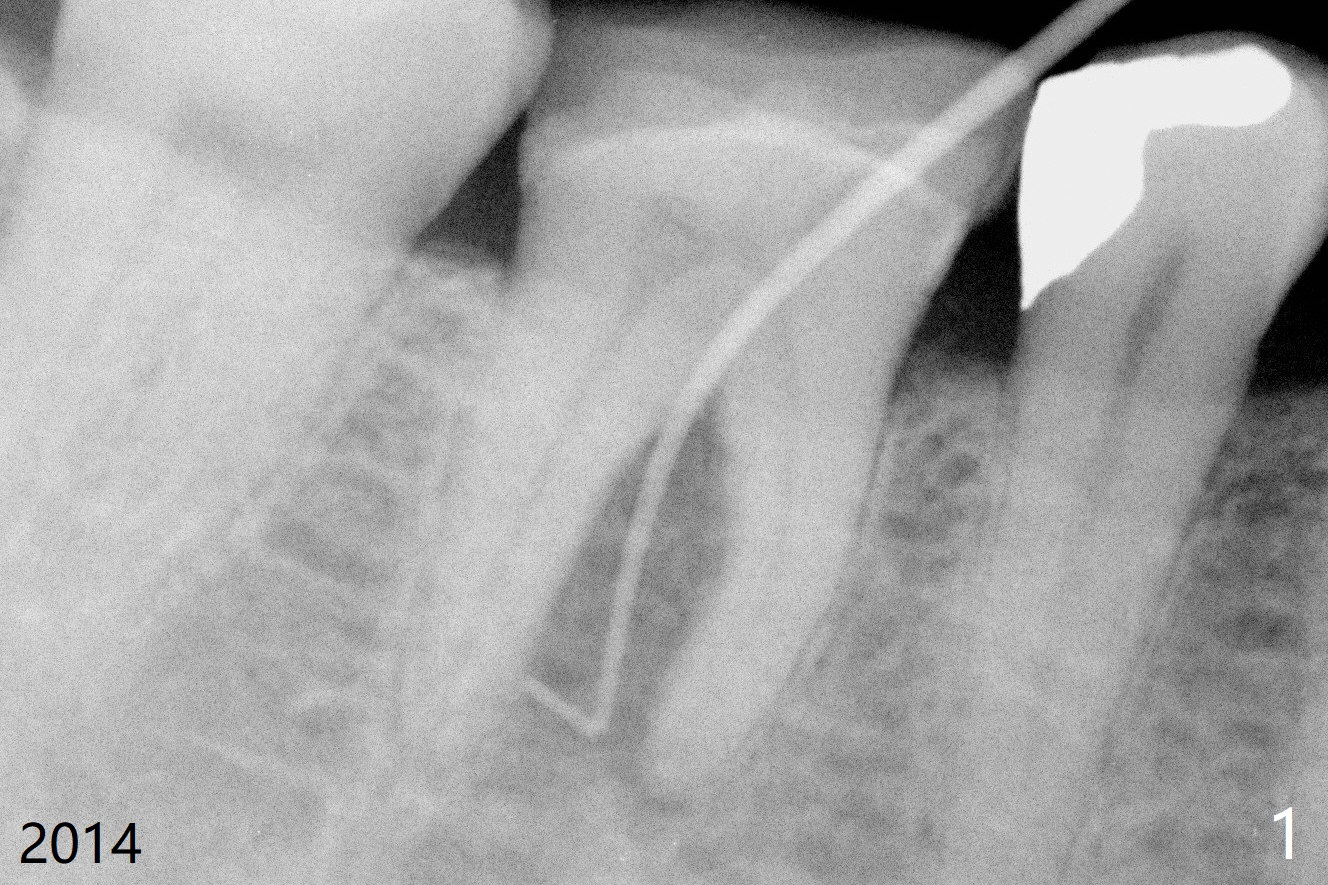

55岁女特别害怕牙科治疗,6年前右下6根分叉以及根尖阴影(图一),根管治疗后3年(图二(阴影消失))才回来做牙冠,现在牙冠因为继发性龋齿而脱落(图三(根尖阴影重现)),病人同意导板即刻种植(图四)。用外科手机去除中隔冠方牙根,完成钻洞后拔除牙根,放入植体。